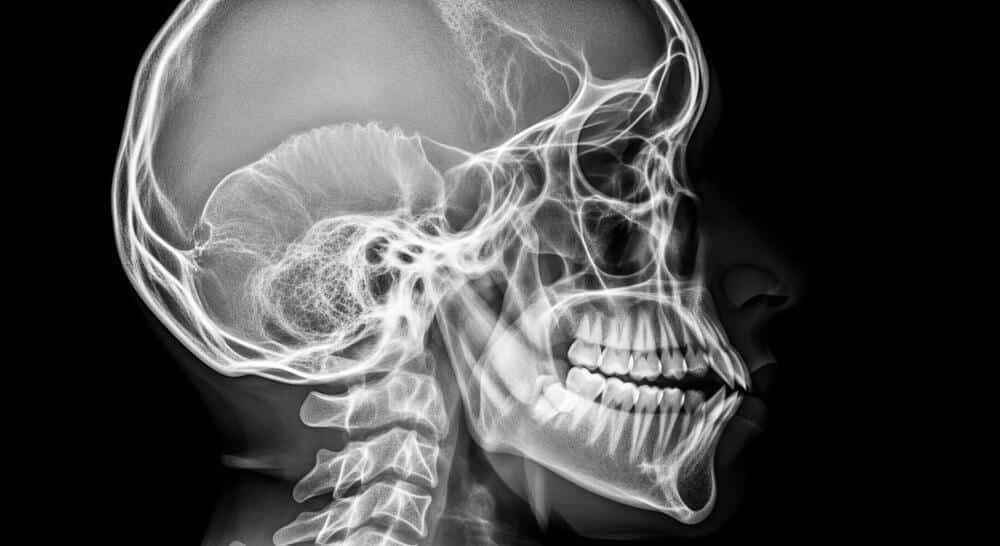

Do You Need a CT Scan or MRI for a Concussion?

Doctors are more likely to order a CT scan when they are concerned about more serious injuries such as bleeding in or around the brain or skull fractures. CT scans are often used in the emergency room when someone has sustained a significant blow, has very concerning symptoms, or takes blood thinners. MRIs are usually reserved for persistent, unexplained, or more complex symptoms that are not improving as expected.

Many concussions have normal CT or MRI scans. A normal scan does not mean you did not have a concussion. Doctors often rely on your symptoms and neurological exam to diagnose a mild TBI. Imaging is one useful tool, but it is not the only way brain injuries are identified.

Yes. You can have a concussion even if your head never struck the steering wheel, window, or airbag. A sudden jolt or whiplash-type motion can cause the brain to move and bounce inside the skull. That movement can stretch and injure brain tissue, resulting in concussion symptoms.